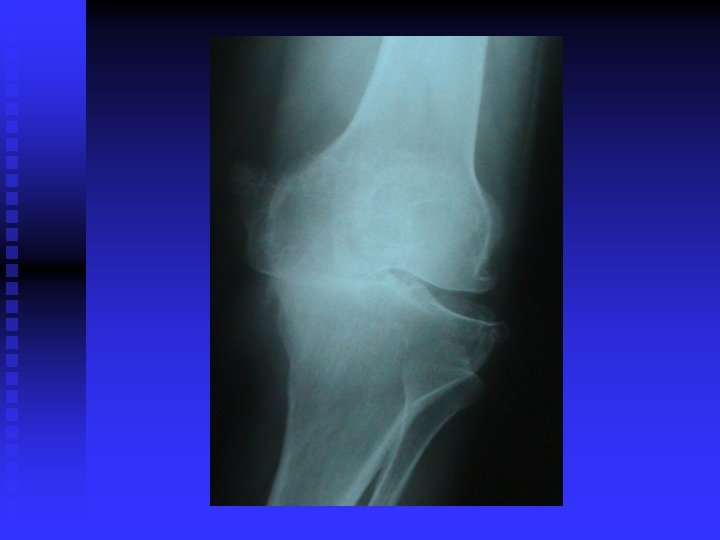

OA RÖNTGEN BULGULARI n Eklem aralığında daralma (kıkırdak incelmiş) n Eklem aralığının kalmaması (kıkırdak bitmiş) n Yük binen yerlerde kistler n Yük binmeyen yerlerde osteofitler